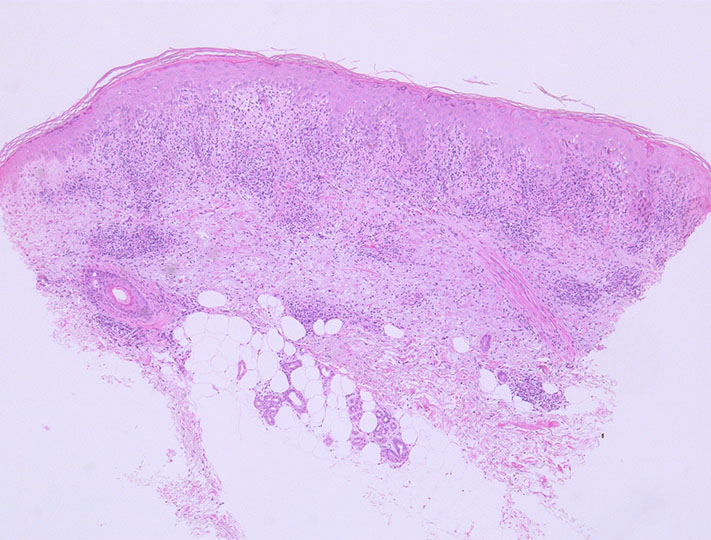

Mycosis fungoidesの皮膚病理

Patch stageでのMF診断は種々の良性皮膚疾患と所見が類似しており鑑別が非常に困難である.診断の"Gold standardは, 臨床所見と病理所見をあわせて診断すること"である.

斑状落屑性紅斑として初発(紅斑期), 数年から数十年後に浸潤性局面を形成(局面期~扁平浸潤期)し, より進行すると腫瘤を形成する(腫瘤期)

表皮内浸潤の最終形態であるポートリエ微小膿瘍(Pautrier's microabscess)形成が有名であるが, この病変が出現する前の早期病変の間に診断することが大切である.--->filePautrier microabscess.pdf

• Pautrier(Pautrier-Darier) microabscess; しばしばcentral Langerhans cellに取り囲まれたT細胞の丸いクラスターで表皮に限局する. patch stageでは通常ない(uncommon)か明瞭ではない(not well-developed)

• Epidermotropism 表皮向性が最重要な所見 (表皮への親和性affinityを示すことで以前はMFにおいて限定して使用されていた(狭義の表皮向性)

• 狭義のEpidermotropism表皮向性にあてはまる5つの所見

• 多数の浸潤リンパ球が表皮内に不均衡に分布する disproportionate epidermotropism

• 表皮に入ったリンパ球が真皮リンパ球よりも大きい large epidermal lymphocytes (emperor sign)

• 表皮に入ったリンパ球がハロー(halo)を有する haloed lymphocytes

• haloをもつ異型リンパ球が基底層に並ぶ(string of pearls distribution ) basilar lymphocytes

• Pautrier's microabscess (Pautrier微小膿瘍)

• 真皮乳頭の線維化 (papillary dermal fibrosis/ wiry collagen); epidermotropismに比べると補助的な所見.

リンパ球表皮向性;表皮内に多数のリンパ球浸潤あり. 核大小不同やくびれを認める. 周囲角化細胞に海綿状態や壊死がほとんどないことが特徴/重要.(MFの表皮リンパ球浸潤パターン)